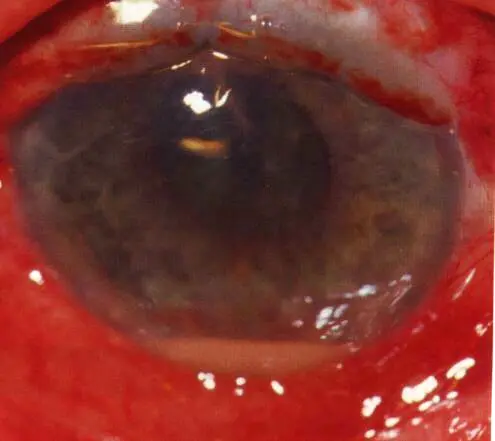

Rubeosis iridis (Abnormal Iris Vessels)

Causes:

- Ischemic central retinal vein occlusion (ICRVO)

- PDR

Complications:

- Rupture of blood vessels leading to hyphema

- Neovascular glaucoma

Treatment:

- Panretinal photocoagulation (PRP) for proliferative diabetic retinopathy (PDR) + valve implantation